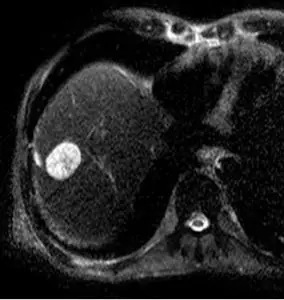

การตรวจหามะเร็งตับด้วยคลื่นแม่เหล็กไฟฟ้า (MRI)

โดยมากจะใช้วิธีการนี้ในบางรายหรือบางกรณีเท่านั้น เช่น รายที่ไม่สามารถตรวจด้วยเอกซเรย์คอมพิวเตอร์ หรือตรวจจากเอกซเรย์คอมพิวเตอร์แล้วไม่ได้คำตอบ หาข้อสรุปไม่ได้

ดังนั้นการตรวจด้วย MRI ใช้เวลาในการตรวจนานกว่า คือ 30 / 60 นาที แต่ไม่จำเป็นต้องงดอาหารก่อนการตรวจ โดยทั่วไปมีราคาค่าตรวจสูงกว่า เอกซเรย์คอมพิวเตอร์เล็กน้อย